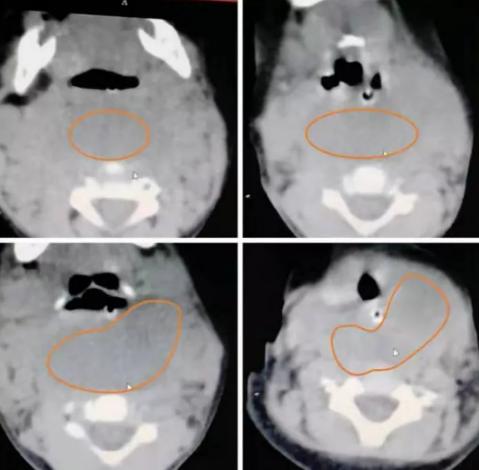

近日,红河州第三人民医院、红河州肿瘤医院妇科团队,成功完成一例罕见巨大左侧前庭大腺囊肿剥除手术,患者术后疗效良好,现已康复出院。术后查阅相关资料,剥除16×7×5厘米的巨大左侧前庭大腺囊肿,目前尚未见国内外文献报道。